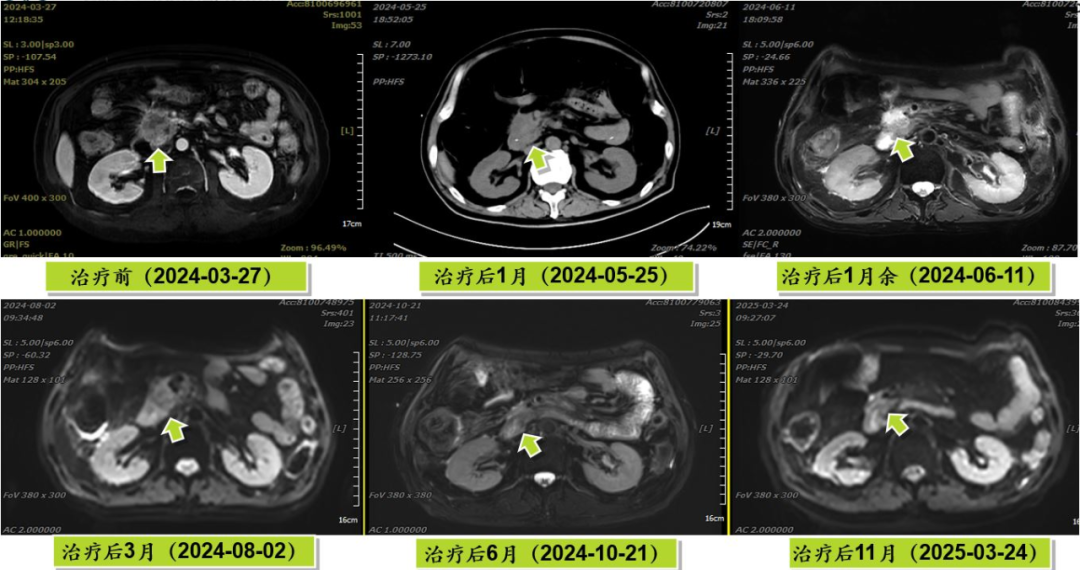

[Treatment Outcome]

CR (Complete Response); After treatment, the patient underwent the following:

- 2024-06-26: Removal of gastrointestinal decompression tube.

- 2024-07-03: Removal of feeding tube, resuming normal oral intake.

- 2024-10: Removal of PTCD tube.

Pancreatic cancer, especially pancreatic head cancer, due to its unique anatomical location, is highly prone to invading surrounding critical tissues and organs, leading to multiple severe complications and posing significant treatment challenges. Reflecting on this case, the patient's pancreatic head tumor had invaded the adjacent descending and horizontal parts of the duodenum, resulting in duodenal obstruction and gastric retention, with frequent vomiting after eating. Concurrently, biliary obstruction caused obstructive jaundice. Furthermore, the patient had multiple comorbid cardiac conditions and poor cardiac function, making the entire treatment process highly complex and demanding.

Carbon ion radiotherapy, as an advanced radiation therapy technology, possesses unique physical and biological properties. It enables precise targeting of tumor tissue while minimizing damage to surrounding normal tissues, offering significant therapeutic advantages for pancreatic cancers in challenging locations that are difficult to resect surgically. However, the application of new technologies is not without hurdles. The treatment team engaged in repeated discussions and research, tailoring a personalized carbon ion radiotherapy plan based on the patient's specific condition, meticulously defining the irradiation field and dosage. Considering the patient's treatment tolerance, four cycles of standard systemic chemotherapy for pancreatic cancer were administered after radiotherapy, ultimately achieving success and allowing the patient to return to a normal life.